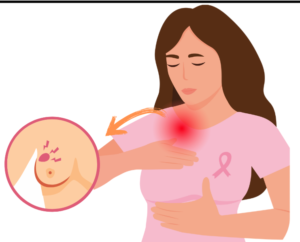

Read MoreBreast surgery

“Breast disease” is a broad term covering a wide spectrum...